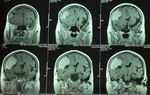

Tuy nhiên, nếu không được điều trị, nhiễm trùng răng miệng có thể lan sang các vùng khác của cơ thể. Chúng bắt đầu từ hàm, cổ, lên đến não. Đó là lúc các biến chứng nghiêm trọng hơn có thể phát sinh. Trong quá trình nhổ răng khôn, những vi khuẩn gây hại này có nhiều cơ hội xâm nhập vào máu và gây nhiễm trùng.